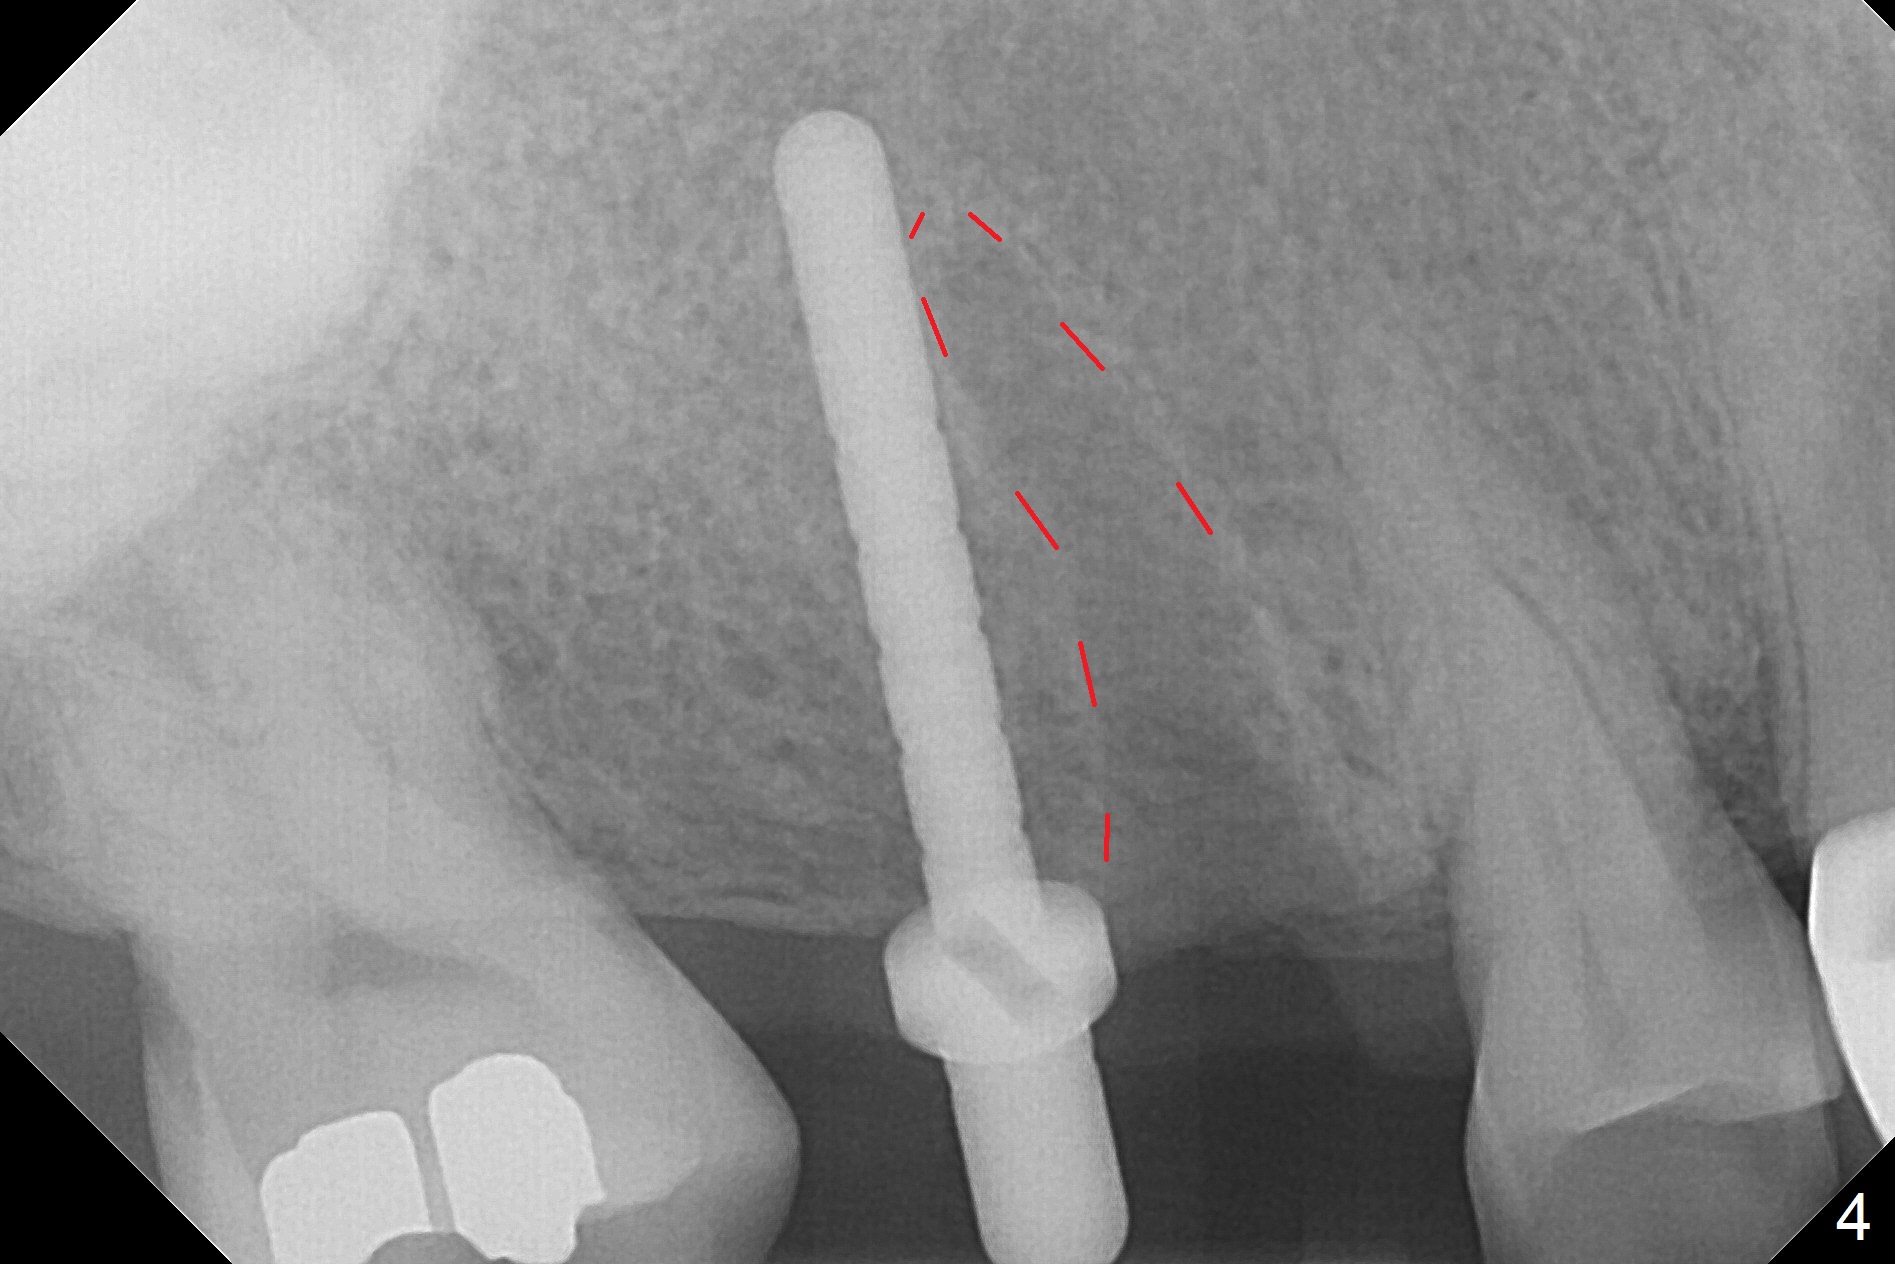

The palatal cusp of the affected 2nd premolar is apparently rotated distal (Fig.1). It is more obvious for the socket (Fig.2): the palatal (P) portion of the socket is more distal than the buccal (B) one. When the gauze is removed (Fig.3), Lindamann bur is used to remove the disto(D)palatal bone of the socket (data not shown), followed by starter drill in the DP wall obliquely (Fig.3'). Once the drill enters the bone for 1-2 mm, the bur is straightened and pushed slightly distal (Fig.3''). Fig.4 shows a parallel pin distal (overcorrect) to the original socket (Fig.4 red dashed line). Sequential osteotomy is conducted until 3.8x13 mm drill for 18 mm (Fig.5): note the 2 steps of the osteotomy (red lines). Since the apical portion of the osteotomy is larger than the drill, a larger implant than expected (5x16 mm) is placed. The implant ends up in the middle of the edentulous area (due to the stepped osteotomy; Fig.6-9; >60 Ncm). Vera allograft is placed (Fig.7-9 *) prior to and after placement of a 6.5x4(3) mm abutment (Fig.8-10). The remaining socket opening is sealed with a piece of Collagen plug (Fig.10 *). The socket is then closed by an immediate provisional (Fig.11 P). The abutment is retightened 2 months postop (Fig.12,13). The crown is cemented 4.5 months postop. Panoramic X-ray and CT are taken nearly 7 months post cementation (Fig.14,15) when the patient is ready for #30 implant guide preparation.